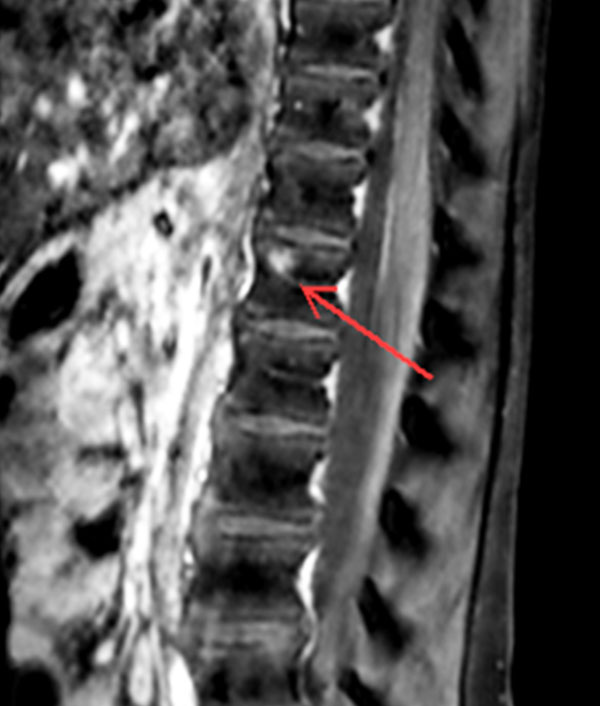

Premium Fat-free Pediatric Spine imaging

Phoenix Children Hospital, USA